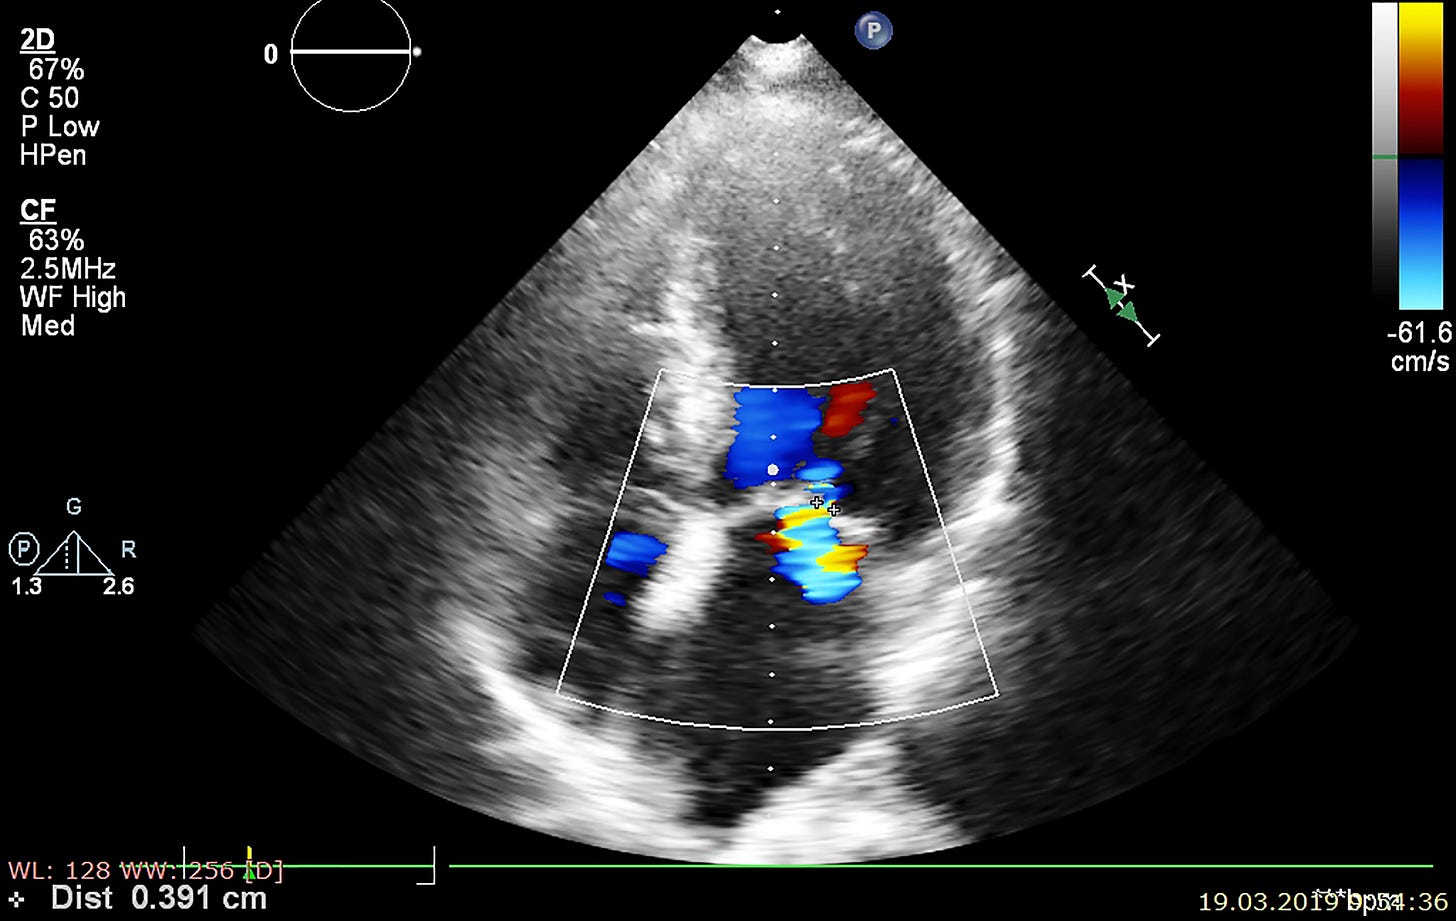

Many clots form in the left atrial appendage; catheter-based closure can prevent strokes by sealing off this part of the heart with a device (Watchman™, PLAATO™, et al). Although LAAC compares favorably to lifelong warfarin, there is limited data on its outcomes relative to treatment with newer anticoagulants.